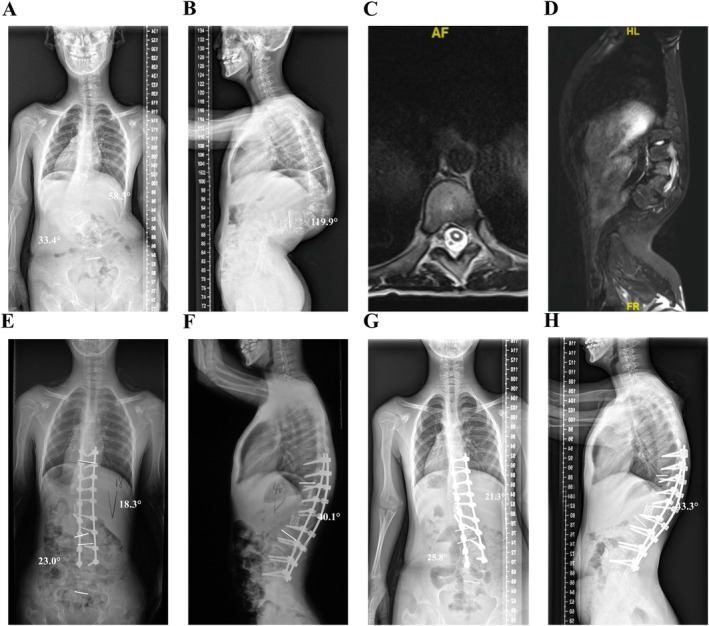

目的:严重的脊柱畸形,包括脊柱侧凸和脊柱后凸,由于神经系统并发症的风险增加,在矫正手术中提出了重大挑战。术前危险因素的识别对于优化预后和预防并发症至关重要。方法:回顾性队列研究分析了2002年1月至2022年5月接受手术治疗的130例严重脊柱畸形患者。全面收集和分析术前临床、影像学和手术资料,目的是确定神经系统并发症的危险因素。进行单因素和多因素logistic回归分析以确定独立预测因素。结果:共纳入患者130例,女性比例50%,平均年龄21.4±15.3岁,其中18例(13.8%)出现术后神经系统并发症。术前脊髓异常(并发症组为38.9%,非并发症组为8.9%,p = 0.001)和较高的后凸角度(并发症组为112.4°,非并发症组为98.2°,p = 0.018)是显著因素。并发症组术中神经监测报警发生率明显高于并发症组(38.9% vs. 15.9%, p = 0.022)。两组手术时间(p = 0.095)和出血量(p = 0.179)差异无统计学意义。较高的后凸角度(OR = 1.027, 95% CI: 1.001-1.055, p = 0.045)和脊髓异常的发生(OR = 6.715, 95% CI: 1.694-26.615, p = 0.007)是手术神经系统并发症的独立预测因素。结论:术前脊髓异常和较高的后凸角度是术后神经系统并发症的独立危险因素。全面的术前评估对于优化这些高危患者的手术策略至关重要。

Results: A total of 130 patients were included in the study, with a female ratio of 50% and a mean age of 21.4 ± 15.3 years, and 18 (13.8%) of them experienced postoperative neurological complications. Significant factors included preoperative spinal cord anomalies (38.9% in the complication group vs. 8.9% in the non-complication group, p = 0.001) and a higher kyphosis angle (112.4° in the complication group vs. 98.2° in the non-complication group, p = 0.018). The incidence of intraoperative neuromonitoring alarms was significantly higher in the complication group (38.9% vs. 15.9%, p = 0.022). No significant differences were observed in operative time (p = 0.095) or blood loss (p = 0.179). A higher angle of kyphosis (OR = 1.027, 95% CI: 1.001-1.055, p = 0.045) and the occurrence of spinal cord anomalies (OR = 6.715, 95% CI: 1.694-26.615, p = 0.007) were independent predictors of surgical neurological complications.

Conclusions: Preoperative spinal cord anomalies and a higher kyphosis angle are independent risk factors for postoperative neurological complications. A comprehensive preoperative evaluation is essential for optimizing surgical strategies in these high-risk patients.